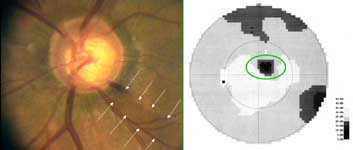

Výpadek proužku nervových vláken začíná temporálně dole od disku, kde je patrná peripapilární hemohagie. V zorném poli výpadku odpovídá horní paracentrální skotom.

Výpadek nervových vláken začíná temporálně dole, kde je na terči patrný zálom vény. Na barevné fotografii není viditelný, protože se jedná o výpadek v hlubší vrstvě nervových vláken, která je překryta vlákny neporušenými. Tato hluboká vlákna směřují do temporální dolní části makuly a v zorném poli jim odpovídá horní nasální skok.

Tento terč má exkavaci protaženou vertikálně a temporálně od obou pólu jsou patrné výpadky nervových vláken. V zorném poli se projevil výpadek vycházející z horní oblasti terče, kde je i peripapilární hemorhagie, jako skotom v nasální dolní části zorného pole s ostrou hranicí v horizontále.